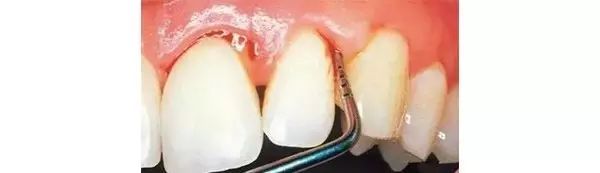

第四步:急性牙髓炎

当您昨晚一夜未眠,牙齿疼得撞墙时,您强忍着说:“吃一颗止痛药吧,再忍忍。”

牙医劝您说:“当病变侵入牙髓组织,产生炎性渗出液,因而形成髓腔高压,引起剧烈疼痛。此时,开髓引流是缓解急性牙髓炎疼痛最有效的方法。”